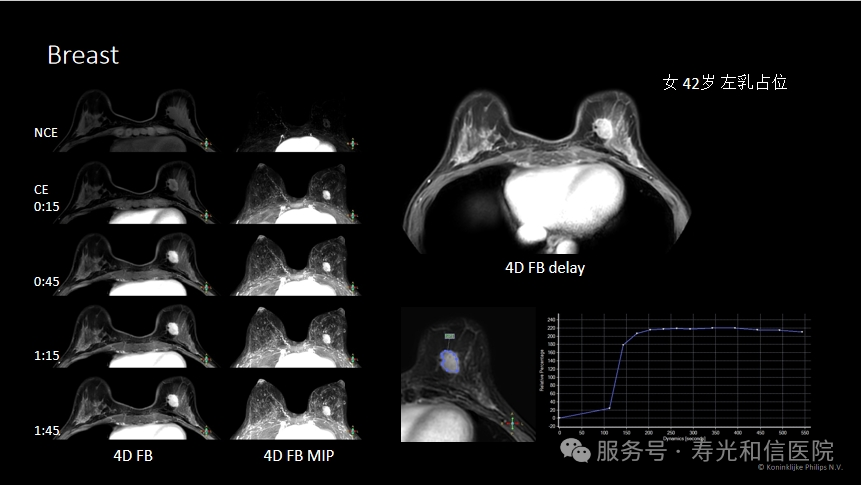

2. 发现早期癌变:MRI对肿瘤的血液供应非常敏感,能捕捉到毫米级的早期癌变或高危病变(如导管原位癌)。

3. 评估肿瘤范围:对于已确诊乳腺癌的患者,MRI能清晰显示肿瘤的实际大小、是否侵犯周围组织,帮助医生制定精准的手术方案。

1. 需要打针:检查前需注射造影剂(增强MRI),以观察肿瘤的血流特点。